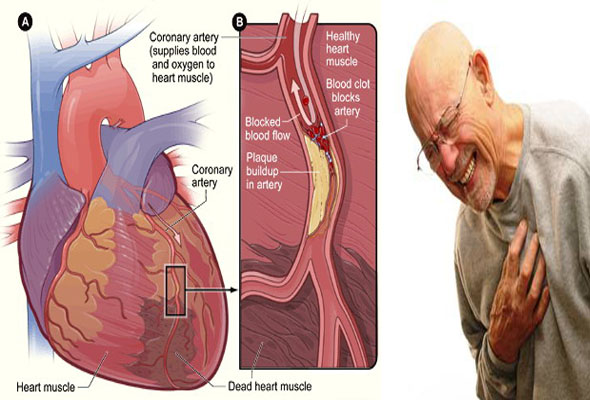

قیمت: 42٬000 تومان - دسته بندی فایل: پاورپوینتپاورپوینت انفارکتوس میوکارد قلب MI

فروش ویژه پاور پوینت حرفه ای انفارکتوس میوکارد قلب MI با تخفیف استثنایی فقط 55 هزار تومان تعداد اسلاید: 19 اسلاید